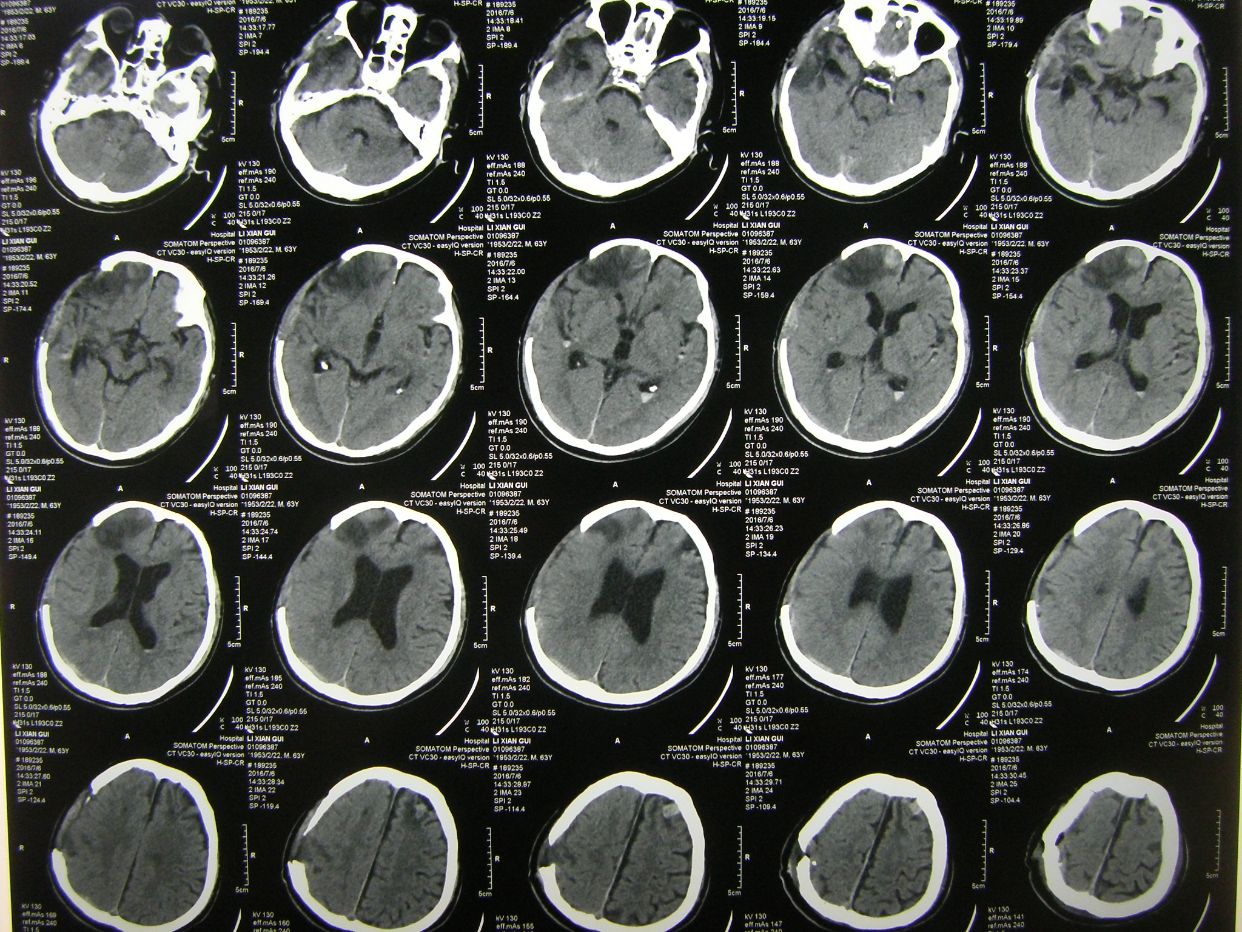

例1,男,61岁,言语不清伴左侧肢体活动障碍1小时入院。

CT示右基底节区脑出血,占位明显,中线移位。因出现右侧瞳孔增大,急症全麻下开颅血肿清除去骨瓣减压。

术后1天CT复查,血肿清除满意,中线恢复。

术后半月CT复查示,水肿基本消退,脑室无扩大。

例2,男,63岁,被发现卧倒在地意识不清半小时入院。

CT示右额颞顶大量硬膜下血肿,右额颞叶脑挫裂伤,中线明显移位。急症全麻下开颅,血肿清除去骨瓣减压术,及气管切开术。

术后CT复查示,血肿清除彻底,中线居中,额颞叶水肿期。

术后3周CT复查,脑水肿消退,中线居中。